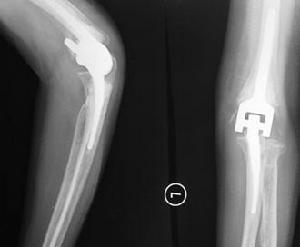

肱骨外髁骨折x片X線照片顯示肱骨小頭的骨折線多超過化骨核的1/2,或不通過小頭化骨核,而通過肱骨小頭與滑車間溝的軟骨在乾骺端處有一骨折線。骨折塊可向外側移位。骨折脫位型X線片,正位片顯示骨折塊連同尺橈骨可向橈側或尺側移位,側位片顯示可向後側移位,偶可見向前移位者。肱骨外髁骨折在X線片上表現為多種多樣,在同一骨折類型中表現也常不一。

4、手術切開復位內固定要使肱骨外髁這種關節內骨折且又是累及骨骺的骨折,最佳地恢復骨關節形態功能,減少骨關節的生長及活動障礙,其最適宜的處理應該是手術切開使其完全解剖復位,然後穩定的內固定。切開內固定主要有:克氏針固定、松質螺紋釘固定,及粗絲線縫合固定等。手術切開復位內固定在直視下操作,有著解剖復位及堅強固定的良好作用,一般在手法或針拔復位不佳時套用,但應注意,手術中應儘量少剝離骨折塊附著的軟組織,以免引起外髁部缺血性壞死和骨骺過早閉合。